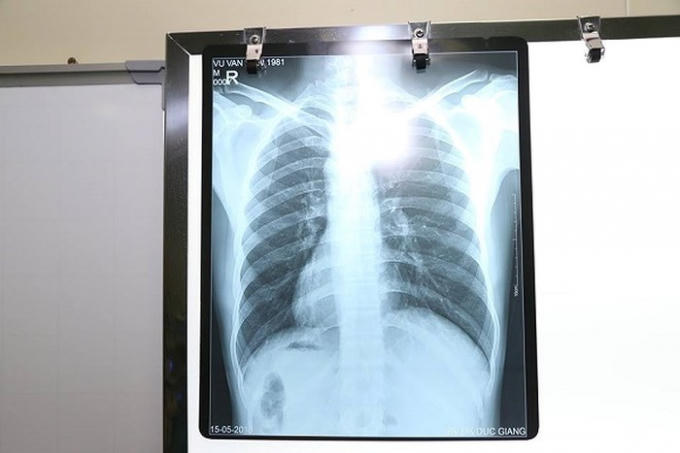

Sau khi thăm khám, xét nghiệm, siêu âm, chụp Xquang, các bác sĩ rất bất ngờ với hình ảnh trái tim cùng với các phủ tạng khác trong lồng ngực và bụng của bệnh nhân H. ở vị trí "soi gương" so với bình thường. Tức là, trái tim và dạ dày ở bên phải, còn gan và ruột thừa thì ở bên trái.

Được biết, đảo ngược phủ tạng là tình trạng bẩm sinh, trong đó các cơ quan nội tạng trong ngực, bụng đảo ngược phản chiếu theo mặt phẳng đứng dọc so với vị trí bình thường. Tình trạng đảo ngược phủ tạng có thể hoàn toàn hoặc chỉ một vài cơ quan đơn thuần.

Đây là một dạng dị tật có tính di truyền gen lặn tương đối hiếm gặp, với tỷ lệ khoảng 1/10.000 dân, trong đó có khoảng 5-10% có dị tật tim bẩm sinh, còn lại có cuộc sống hoàn toàn bình thường.